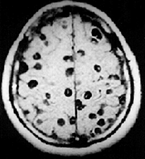

Paciente

masculino de 9 meses de edad quien es llevado por la madre a la emergencia

porque ha notado que su hijo está “un poco cabezoncito” a comparación de sus

hermanos mayores a esa edad. Mencionan que viven como criadores de cerdo y

consumen las sobras de la carne que no se vende, incluso de forma cruda. Al

examen físico se encuentra al paciente como en la foto y se confirma que hay

quistes o calcificaciones de tipo infeccioso en el conducto de Silvio… ¿Cuál es

el patógeno responsable de la clínica de este paciente? (género y especie)